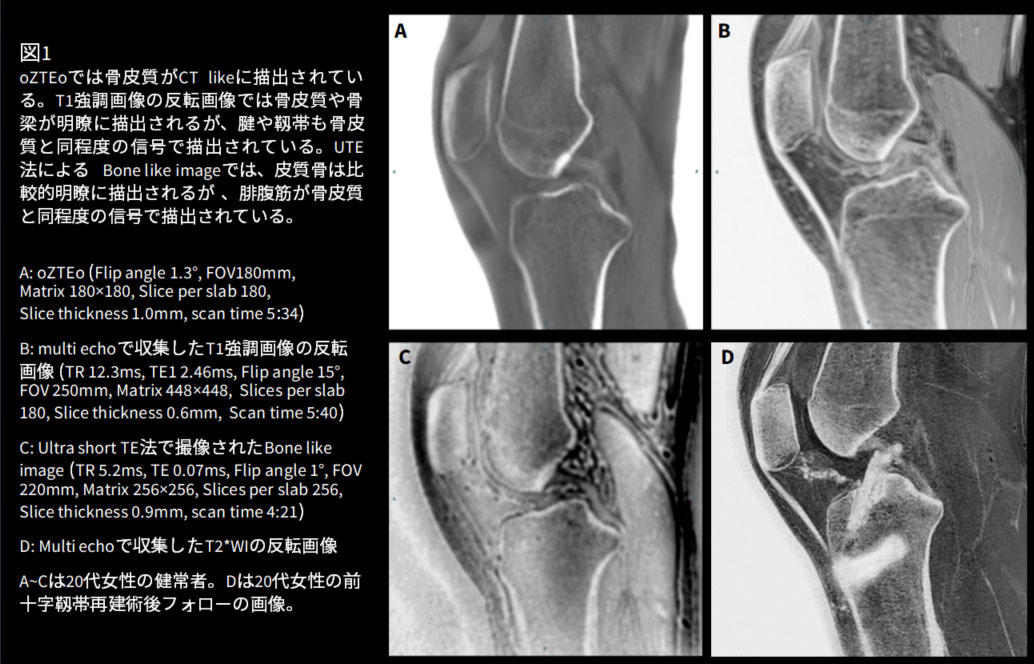

症例1は後縦靱帯骨化症の症例です(図2)。T1強調画像やT2強調画像だけでは骨縦靱帯の肥厚と骨化を区別できないことがしばしばありますが、oZTEoを追加することで骨化した後縦靱帯が明瞭に描出されます。